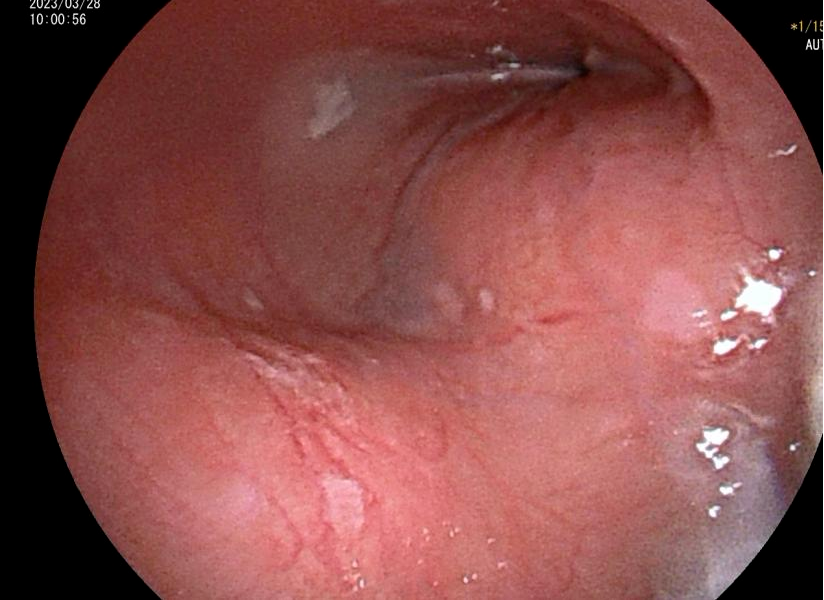

治疗前,杨浩贤主任医师为古先生安排了全面细致的术前检查。胸腹部CT检查结果提示,食管胸下段管壁不均匀环形增厚,最厚处达42mm,长约81mm,与胸主动脉相贴;超声胃镜检查确认了在距离门齿约35-40cm处,可见食管近全周粘膜下隆起肿物,表面粘膜光滑,起源于食管固有肌层,累及食管全周,病情非常复杂。

术前超声胃镜检查发现食管几乎完全堵塞